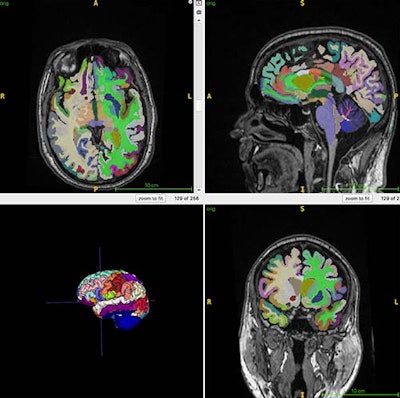

This color-coded brain figure shows an example of segmented regional volumes obtained from the 3D T1 volumetric MRI scans used for the artificial intelligence (AI) computations of brain age used in this study.This color-coded brain figure shows an example of segmented regional volumes obtained from the 3D T1 volumetric MRI scans used for the artificial intelligence (AI) computations of brain age used in this study. RSNA